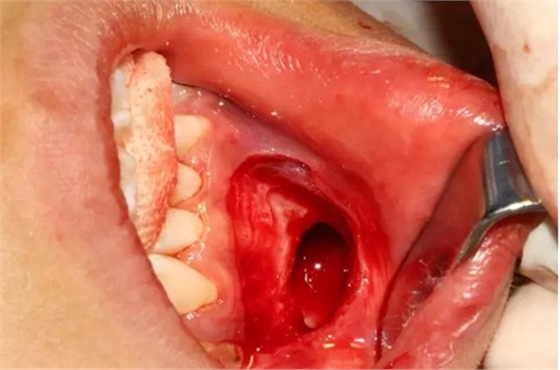

本案:患兒,女,14歲,因牙齒矯正來(lái)院,檢查見(jiàn)83滯留,43未見(jiàn)萌出,拍片發(fā)現(xiàn):43埋伏阻生于31、41、42根尖下方,按照正畸診療計(jì)劃,擬行43拔除術(shù)。

切開(kāi)、翻瓣

去除骨皮質(zhì),暴露牙冠大部分